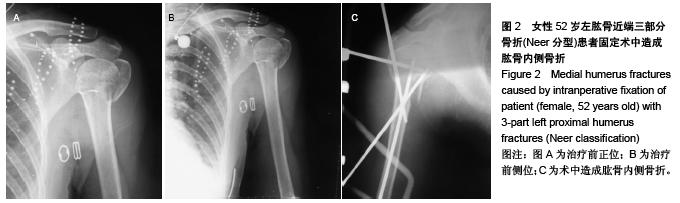

Novel closed intersection nailing external fixation repairs proximal humerus fractures: 6-month follow-up

Huang Hai-jing, He Jin-quan, Wang Jie, Jin Hong-bin. Novel closed intersection nailing external fixation repairs proximal humerus fractures: 6-month follow-up[J]. Chinese Journal of Tissue Engineering Research, 2015, 19(48): 7795-7800.